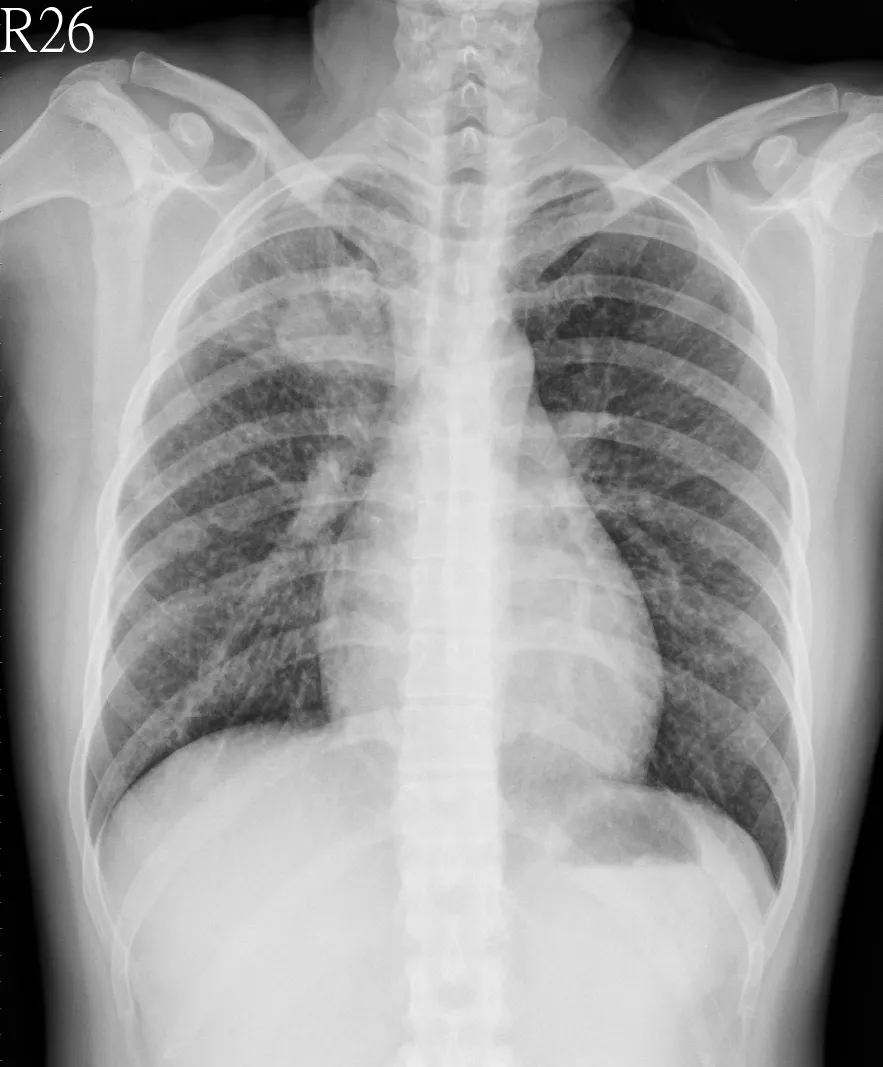

破題關鍵

這張胸部X光片顯示兩側肺部廣泛性的網狀結節狀浸潤,搭配病患長期咳嗽和體重減輕的症狀,強烈暗示惡性腫瘤的可能性,尤其是肺癌的瀰漫性表現或淋巴管癌病變。

選項拆解